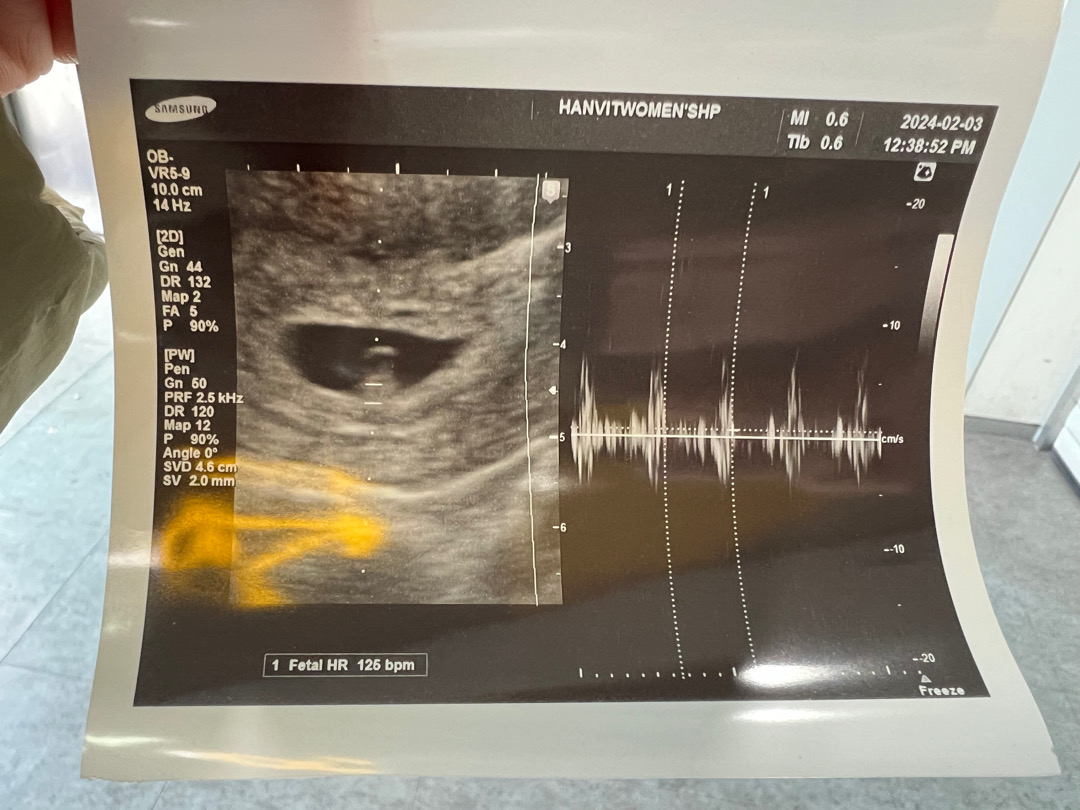

오늘이 6주5일 되는 새해맘이에요 ㅎ 저는 심하지는 않지만 먹덧증상이 계속 있었거든요! 아침에 일어나면 배고파서 속이쓰리고 배고픔을 못참을정도로 허덕였는데 ㅋㅋㅋㅋㅋ 또 배고파서 뭘 먹으면 속이 더부룩하고 소화안되고.. 퇴근하고 집에와서 누우면 배콕콕 증상도 쭉 있었어요 근데 이틀 전부터 뭔가 먹덧증상이 없어진 느낌이고 배콕콕 거림도 없는 느낌.... 증상이 있으면 힘들고, 없으면 또 걱정되고 다들 같은 마음이잖아요ㅠ 병원은 다음주에 예약인데 아가는 궁금하고.. 그래서 베동도 엄청 찾아보고 ... 혼자 마음조리고 있었는데 안되겠더라구요ㅠㅠㅠ 오늘 그냥 병원 다녀왔어요 ㅋㅋㅋ 심장소리를 아직 못들었어서 걱정이었던건데 정말 다행히 잘 자라고 있더라구요!!! 5주 3일때엔 아기집이랑 난황만 봤는데, 일주일만에 만난 새해는 0.3센치로.... 귀염뽀짝하게 자라있었어요😍 심소도 듣구요!!! 아기집만 확인하고 심소 못들었을때 2주 뒤에 오라고 하는거 너무 가혹한것.... 베동 보니까 저처럼 입덧증상 갑자기 없어지는 경우가 많이 있는거같은데 너무 마음조리면서 걱정하지말고, 스트레스 받지말고 좀 일찍 병원 다녀오시는거 추천해요!!! (진짜 속이 후련...)